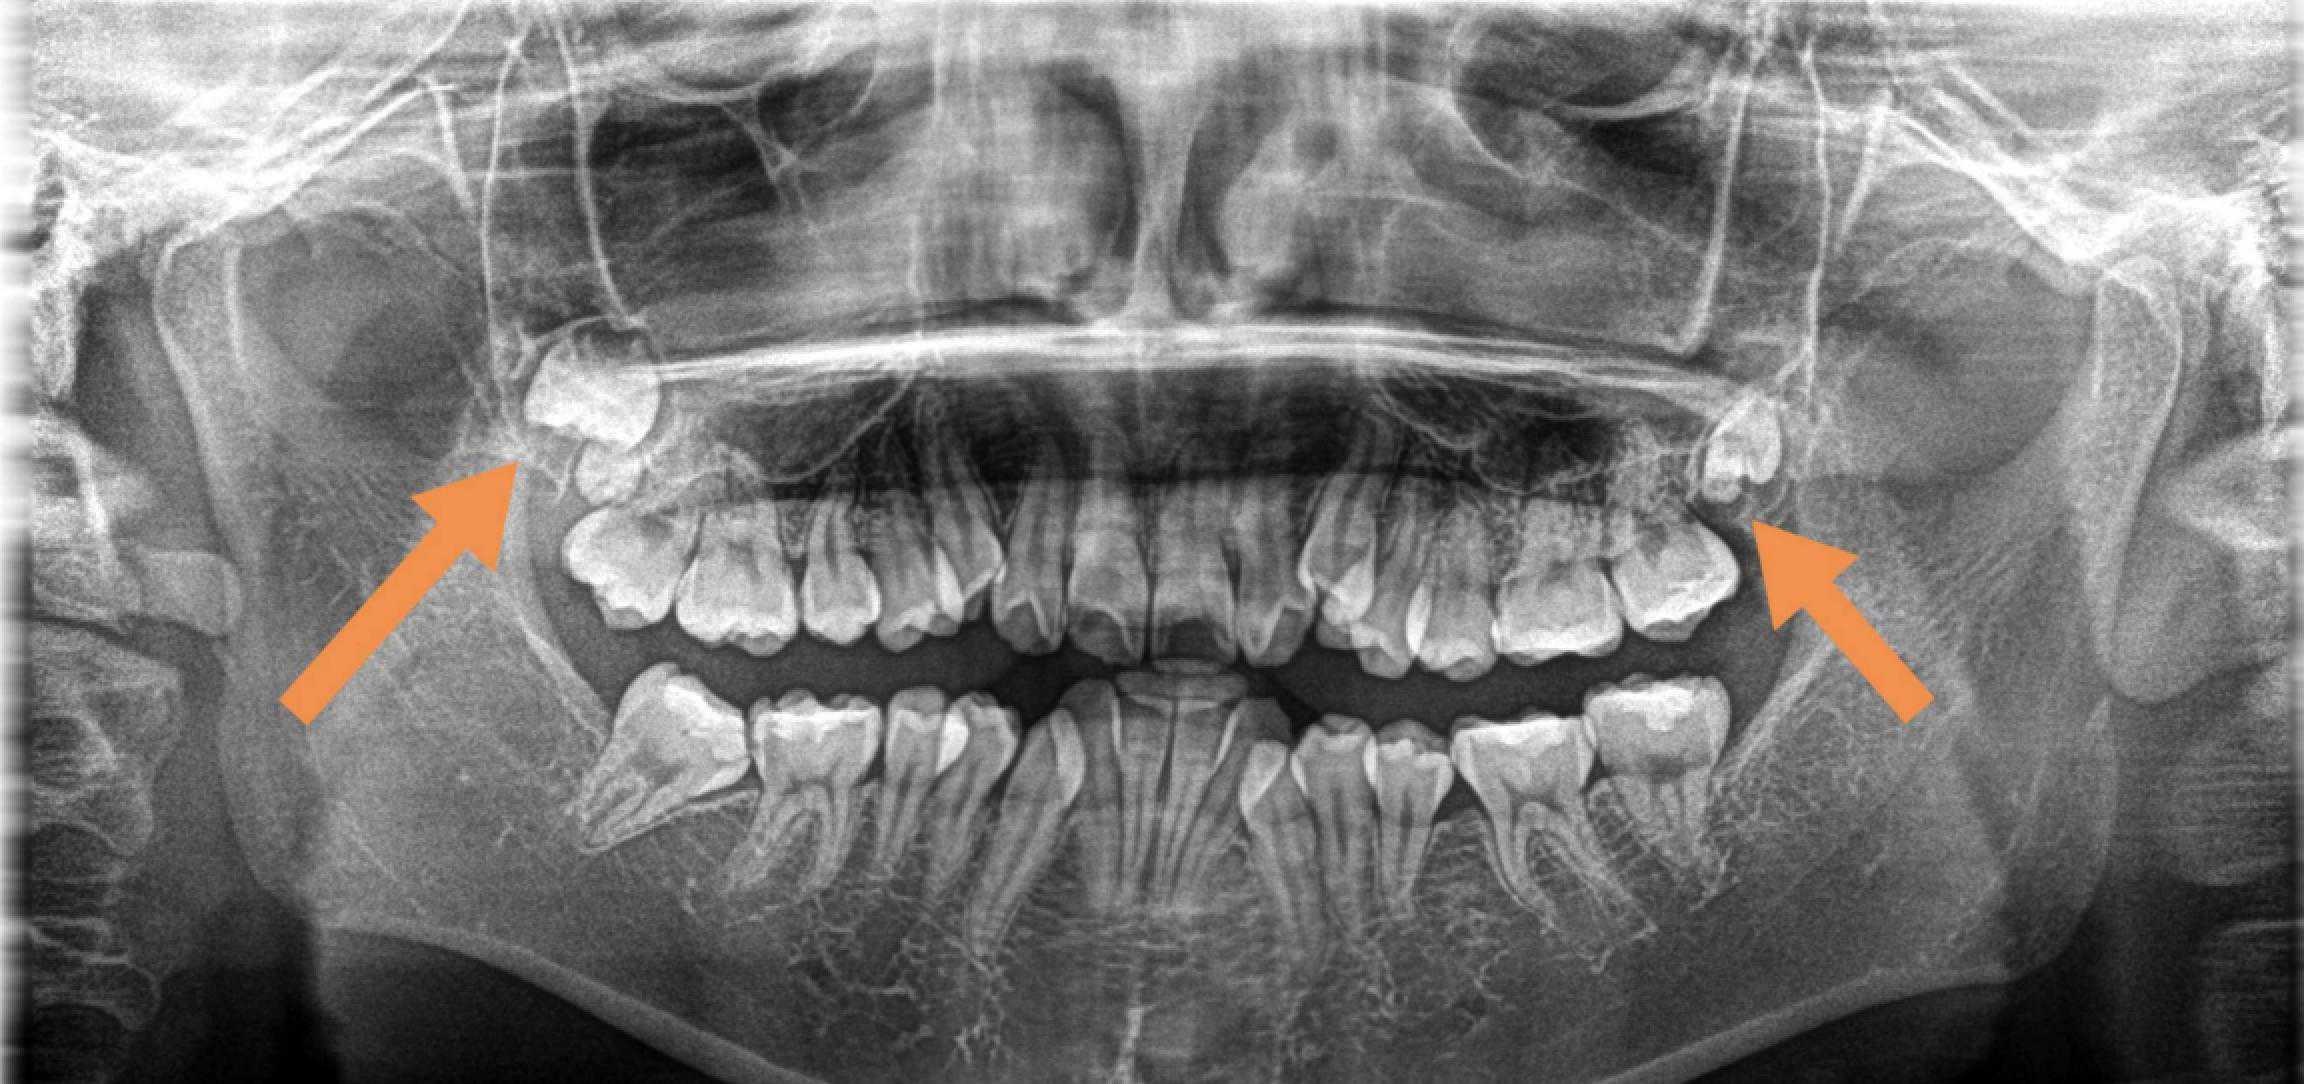

③拔除斜长、横长或埋在骨头里的下颌智齿,难度系数:★★★★

其实,这些就是我们俗称的阻生牙。

这一类智齿比较难拔,基本上都是微创手术了,但也需要切开牙龈操作,手术难度还是不低的。因此价格相比前两种手术会高一些。

下颌智齿水平生长

当然,还有其他更加奇奇怪怪的pose……

各类“不听话的”下颌智齿

拔牙前拍X光片可以让医生看到肉眼看不到的牙根形态、生长状态。

根据X光片的结果,医生可以更全面地评估拔牙的难度,定制拔牙的方案,向患者更好地解释一些可能存在的风险。